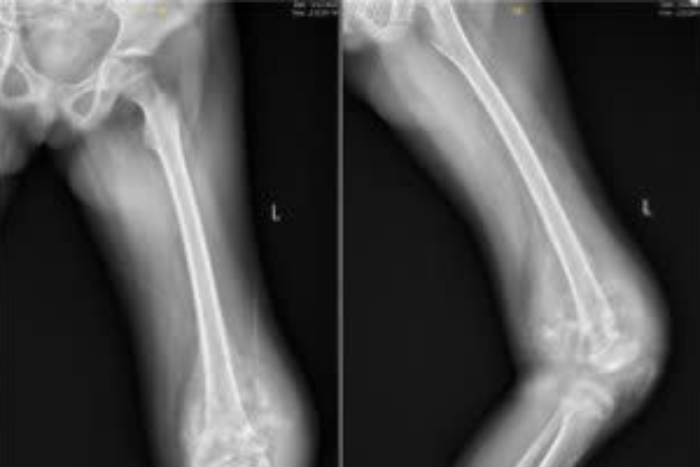

Bé gái 8 tuổi ở Hà Nội mắc ung thư ác tính từ sưng mắt cá chân

Bị sưng mắt cá chân tưởng do ngã khi chơi, bé gái 8 tuổi ở Hà Nội được chẩn đoán mắc ung thư sụn tái phát, xâm lấn toàn bộ mắt cá ngoài. Ca phẫu thuật kéo dài 8 giờ đã giúp bệnh nhi giữ được chi và khớp cổ chân.